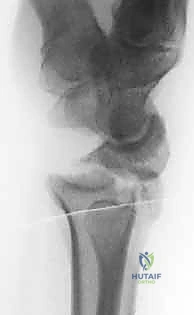

- كسور داخل المفصل (Intra-articular): الكسر يمتد ليشق السطح الغضروفي للمفصل (وهنا تبرز الأهمية القصوى لاستخدام المنظار).

الخطوة الرابعة: رد الكسر تحت الرؤية المباشرة

باستخدام أدوات دقيقة، يتم تحريك القطع العظمية المكسورة وإعادتها إلى مكانها الطبيعي. يراقب الجراح العملية عبر شاشة المنظار ليتأكد من أن السطح المفصلي أصبح مستوياً تماماً بنسبة 100%.

الخطوة الخامسة: التثبيت الداخلي

بمجرد استعادة الشكل التشريحي، يتم تثبيت العظام. قد يتم استخدام أسلاك كيرشنر (K-wires)، مسامير دقيقة، أو شريحة معدنية داعمة (Volar Plate) توضع من خلال شق صغير منفصل لضمان ثبات الكسر التام. يتم أيضاً خياطة أي تمزق في الأربطة إن وجد.